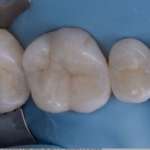

La diagnosi cavitaria in conservativa: un modello dinamico di terapia

Viene preso in esame un caso clinico, con riabilitazione di più elementi dentari, che gli autori hanno effettuato utilizzando restauri parziali in composito con...